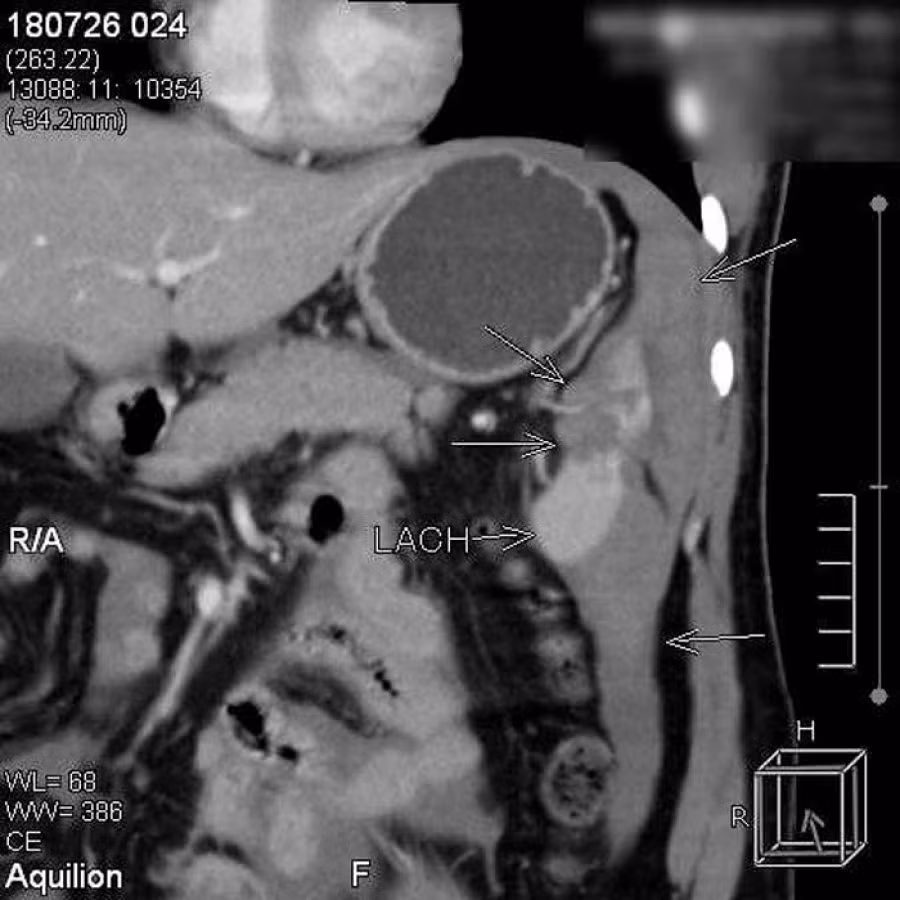

Bệnh nhân giữ được lá lách nhờ phương pháp điều trị ít xâm lấn